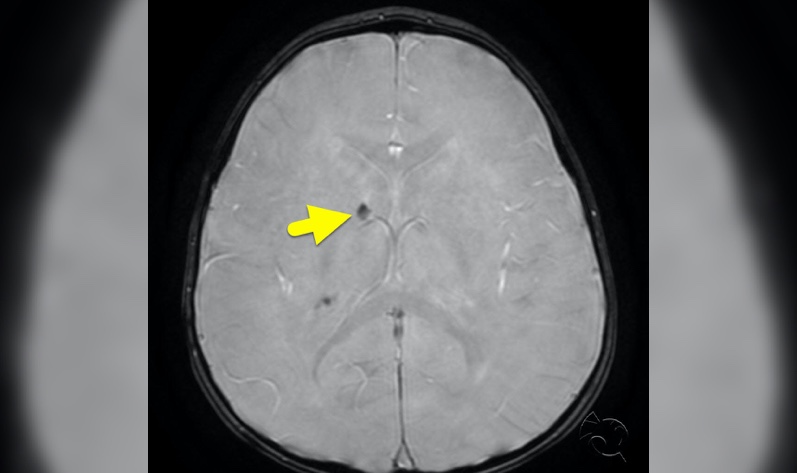

Physical exam is normal except hypomelanated “ash leaf spots” and periungual hamartomas (Koenen toes), as pictured. An MRI done as part of the seizure workup shows subcortical white matter changes (a “tuber”) on T2 and subependymal nodules on SWI, or susceptibility weighted imaging.

Figure 1 medical case: Tuberous Sclerosis Complex Imaging